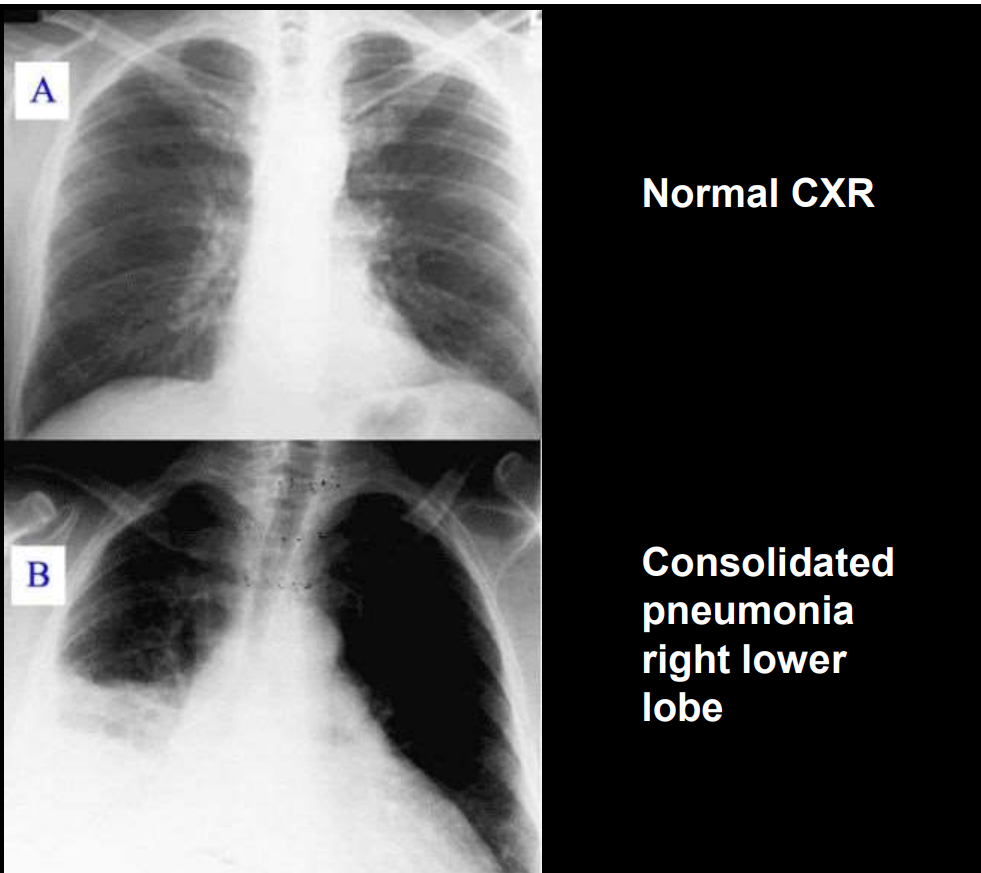

• Pneumonia Chest Xray:

A) pneumonia

• This airless state is called consolidation